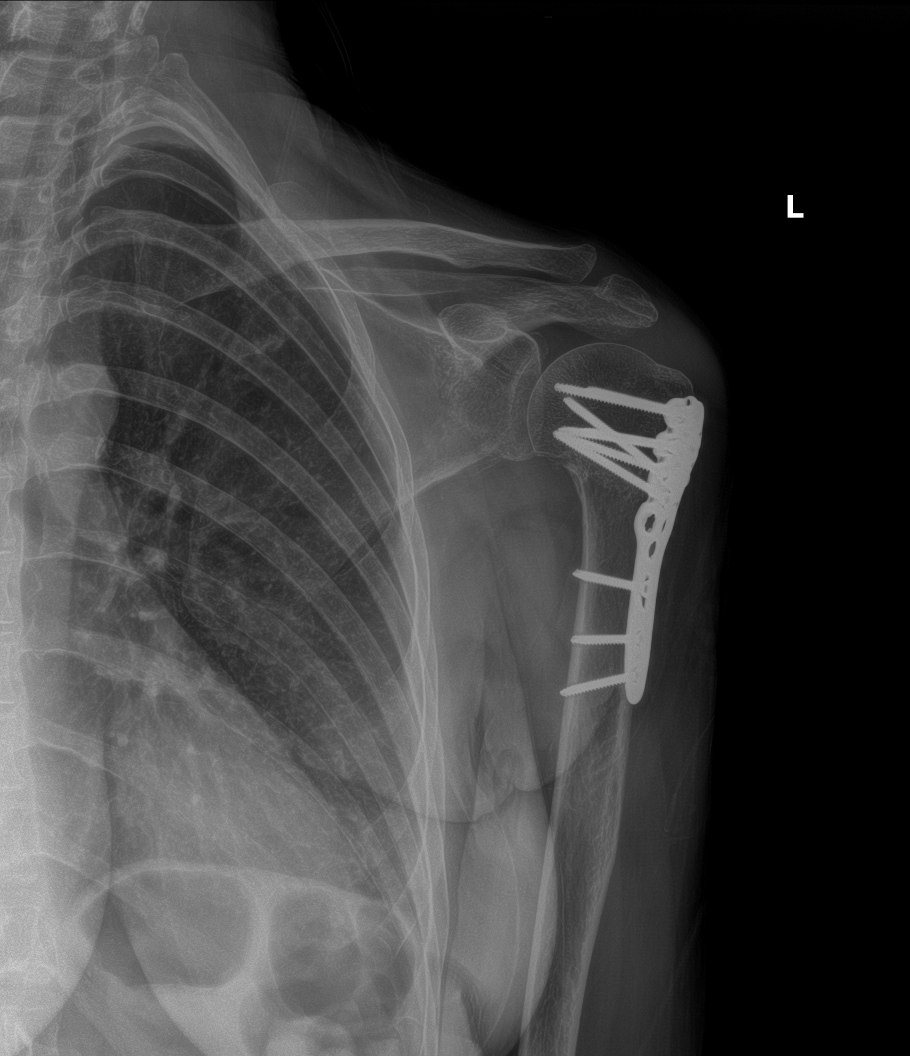

Unfortunately, over the next couple of weeks Mrs. A’s shoulder pain got worse. The doctor ordered more x-rays, which showed that the broken bone was now out of alignment. He informed Mrs. A that she would now need surgery to repair the fracture. She underwent the surgery, called an open reduction internal fixation surgery. It involved using a metal plate and screws to secure the fracture and correctly align it while it healed. Here are x-rays of her shoulder after the surgery: